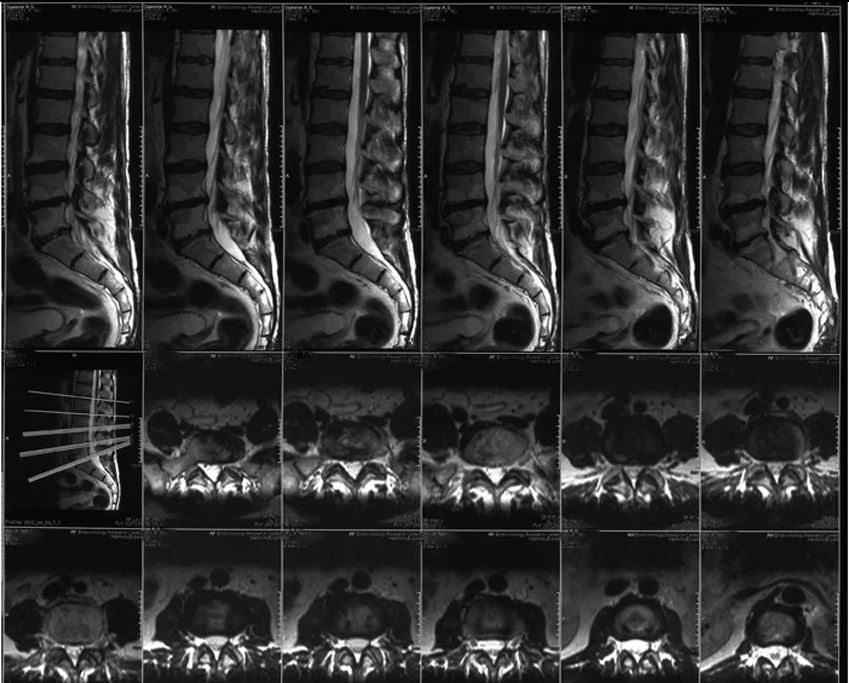

Используйте снимки в разных проекциях, чтобы получить более полное представление о состоянии позвоночника.

Сравнивайте снимки с нормальными изображениями, чтобы выявить аномалии.

Обратите внимание на состояние межпозвоночных дисков, чтобы оценить наличие протрузий или грыж.